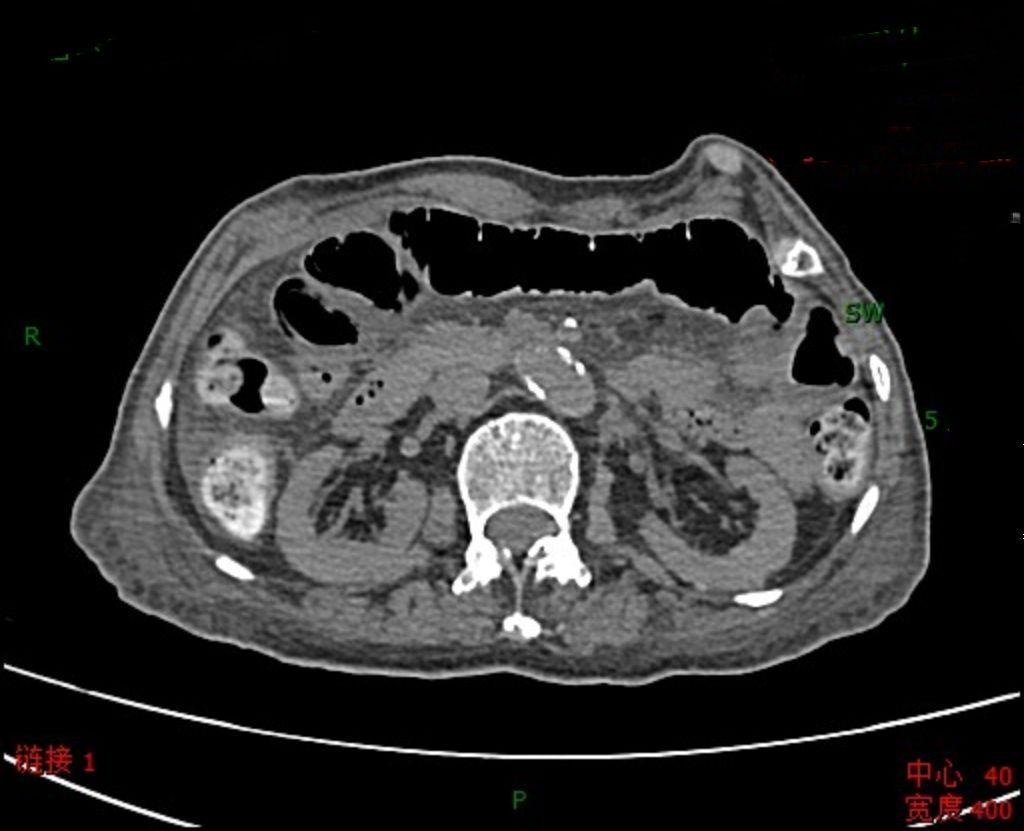

小肠梗阻,有时候略显隐蔽的腹痛